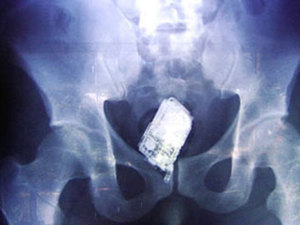

South Korean customs officials say they have arrested eight men over a scheme to allegedly smuggle gold out of the country by hiding it in their rectums.

The Korea Customs Service said Monday the men allegedly transformed $260,000 in gold bars into small beads and smuggled them in their rectums to Japan two times in 2010 to avoid import taxes.